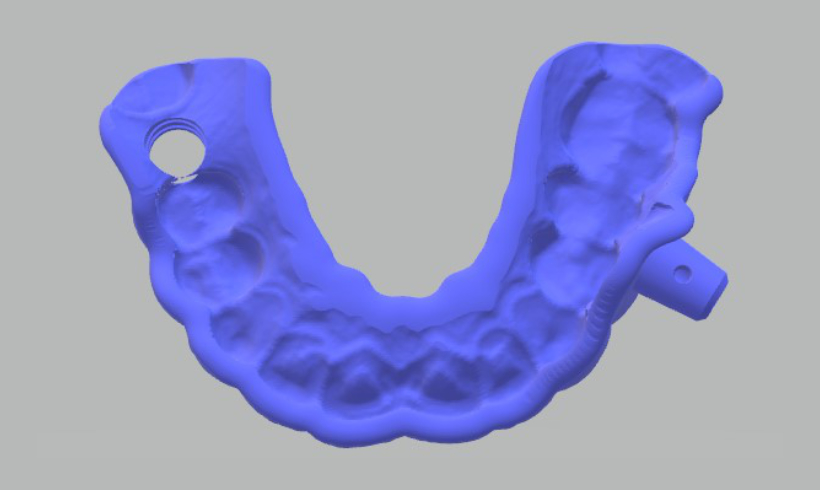

Guías quirúrgicas

Las guías quirúrgicas previa correcta planeación mediante todas nuestras herramientas de diagnóstico clínico y digital, nos permite disminuir el porcentaje de errores clínicos.